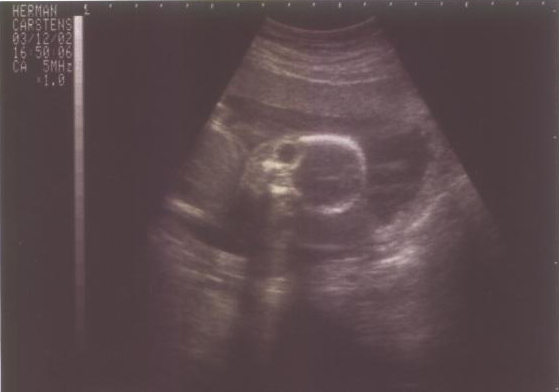

17

Semanas |